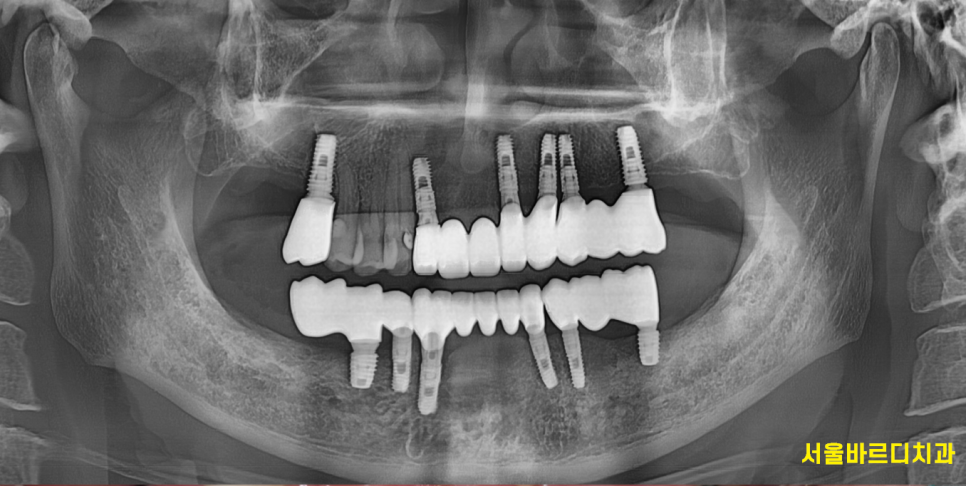

240513

뿌리만 남은 치아

충치가 심한 곳들

잇몸이 안좋아 흔들리는 부분

정리할 치아들은 발치 후

위,아래 임플란트를

앞니 어금니 임플란트 동시에 수술했습니다.

하루에 치료해드렸는데요~

이렇게 되면 수술에 대한 부담감도 덜어드릴 수 있고

치료기간도 현저하게 줄어들죠~